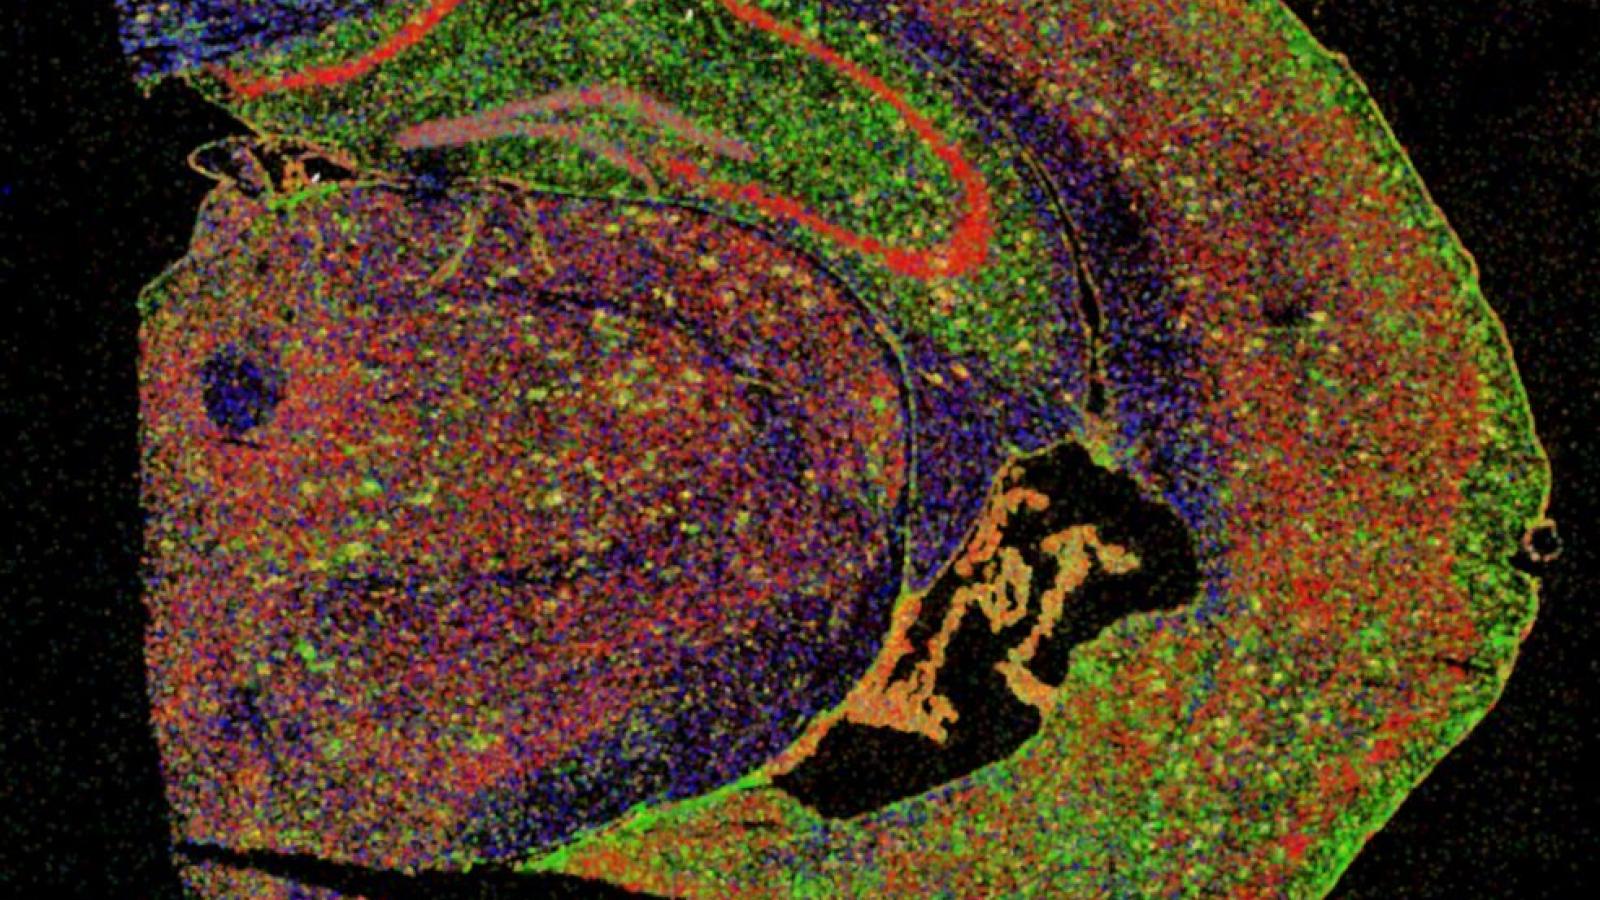

Researchers led by Prof Bart De Strooper (UK DRI Director) and Dr Mark Fiers at the VIB-KU Leuven Center for Brain & Disease Research in Leuven, Belgium, have used pioneering technologies to investigate what happens in brain cells in the direct vicinity of protein plaques in Alzheimer’s disease. Using a mouse model of the condition and human brain tissue, the team’s findings suggest that brain cells work together to first provide a protective response that becomes damaging in the later stages of the disease. The results may help to determine the optimal window of opportunity to therapeutically intervene during disease progression.

One of the hallmarks of Alzheimer’s disease is the accumulation of the protein amyloid beta (Aβ) into plaques around neurons. Genetic evidence suggests that Aβ may play a key role in the development of the condition and the eventual death of neurons in the brain. Decades of research have sought to uncover the precise events occurring, though many questions still remain. In this latest study, published today (22 July) in Cell, researchers turned to advanced technology in ‘spatial transcriptomics’ to decode the molecular changes in cells near to the Aβ plaques.

Performing analysis within a 100-micrometre perimeter – around the diameter of an average human hair – of the plaques, the researchers discovered that the cells were producing Ribonucleic Acid (RNA), instructions for making proteins, in two broad profiles during the course of the disease.

In what would be the early or mild stages of Aβ build-up in the mouse model of disease, the team found that genes were enriched in a particular cell in the brain, oligodendrocytes, whose main role involves supporting neurons with the rapid transmission of electrical signals. The team speculate that this profile may be protective, possibly involving repair to the brain.

However, as the Aβ continues to accumulate, the researchers observed a different profile of gene expression involving 57 plaque-induced genes (PIGs) from several support cells such as microglia and astrocytes. This profile was associated with increased inflammation and oxidative stress, perhaps indicating that cells in the brain were being overwhelmed by the increasing Aβ plaques. Dr Mark Fiers, co-lead of the study, noted that many of the genes in both these profiles or networks were similarly altered in the human post-mortem brain tissue, supporting clinical relevance from the mouse model of disease.

Image courtesy of the De Strooper Lab -Section of half a mouse brain in which different types of brain cells are stained